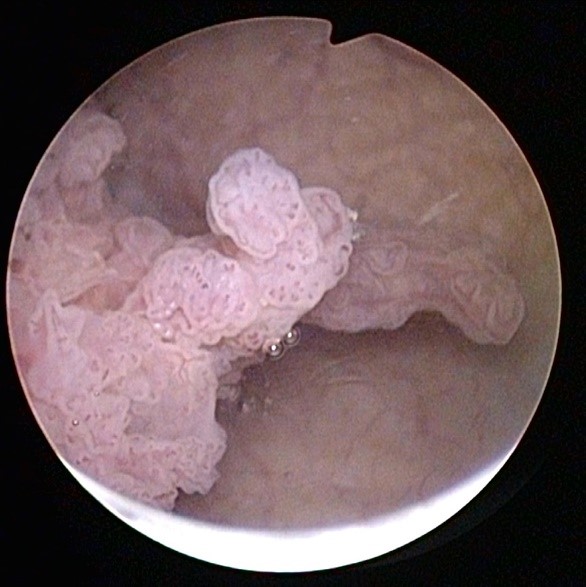

Es gibt 2 Arten des Blasenkrebs bzw. Urothelkarzinoms: den Korallenförmig wachsenden sogenannten «papillären» Blasenkrebs und das flächig-flach wachsende sogenannte «Carcinoma in situ», welches oft sehr aggressiv ist.

| 2 Ansichten bei der Blasenspiegelung (Zystoskopie) auf bösartige Blasentumore, welche korallenförmig (Fachausdruck: exophytisch) in die Harnblase hereinragen. | |